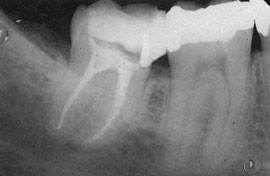

Пломбирование корневых каналов

Успех пломбирования корневых каналов в значительной степени определяется качеством выполнения предыдущих эндодонтических манипуляций, и в основном, обуславливает исход проводимого лечения.

Основным требованием этого этапа является надежность герметизации корневых каналов. Перед пломбированием каналы высушиваются бумажными штифтами.

Для заполнения корневых каналов используют гуттаперчу и пасту. Гуттаперча - резиновый материал, который производится в виде конусов, размер и форма гуттаперчи соответствуют форме и размеру файлов, при помощи которых вычищают корневые каналы.

Конусы из гуттаперчи покрываются пастой и вводятся в корневые каналы зуба. Для получения хорошей герметизации, в корневые каналы вводятся еще несколько конусов.

После пломбирования корневых каналов, стоматолог ставит временную пломбу на отверстие, которое было сделано для достижения в области корневых каналов.

Канал должен быть запломбирован до верхушки и без пустот и дефектов.